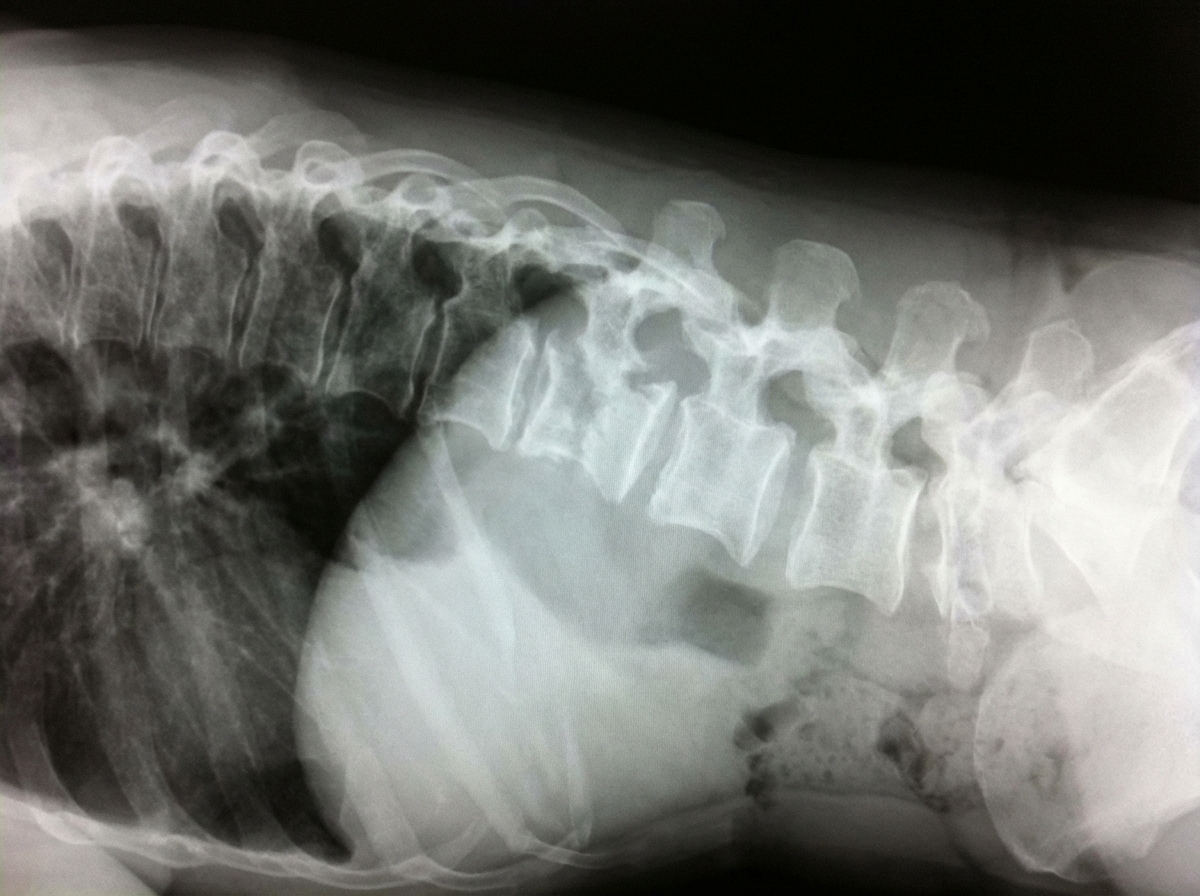

Which of the following is the most probable diagnosis of the patient with the given X-ray?

Explanation: ***Pott's spine*** - X-ray shows characteristic **disc space narrowing** and **vertebral collapse** with **paravertebral shadow**, pathognomonic of tuberculous spondylitis. - May demonstrate **gibbus deformity** (angular kyphosis) due to anterior vertebral body destruction with relative disc space preservation initially, then progressive narrowing. *Osteoporosis* - Presents with **generalized bone demineralization** and **compression fractures** but **disc spaces remain preserved**. - Lacks the **paravertebral soft tissue shadow** and focal destructive changes seen in infectious processes. *Metastatic bone disease* - Typically shows **multiple lytic or sclerotic lesions** throughout the skeleton with **preserved disc spaces**. - **Pedicle destruction** ("winking owl sign") is common, but disc involvement is rare unlike infectious spondylitis. *Multiple myeloma* - Characterized by **multiple punched-out lytic lesions** in vertebral bodies with **normal disc spaces**. - Often associated with **pathological fractures** but lacks the paravertebral soft tissue involvement typical of Pott's spine.